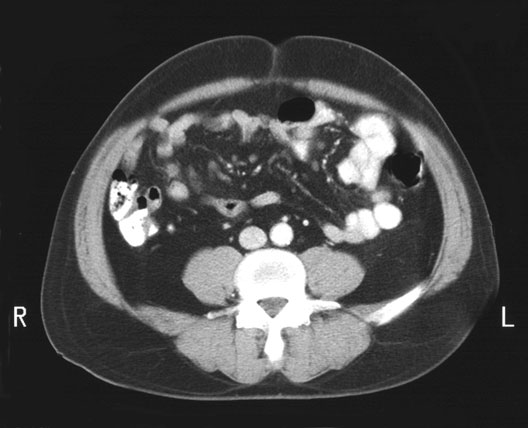

Inferior Mesenteric Artery

1. Right Colic (Hepatic) Flexure

2. Inferior Vena Cava

3. Colon

4. Inferior Mesenteric Artery

5. Aorta

6. Psoas Muscle